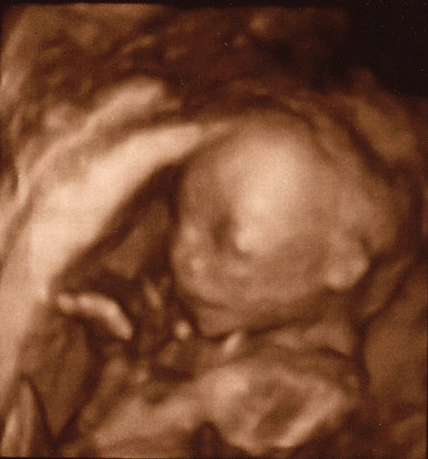

It’s a girl! It was so incredible to see her on the ultrasound – I still can’t believe this beauty is in my belly. I fell so madly in love the second her little face came up on the [huge] ultrasound screen, I almost forgot about the firepoker that seems to have lodged itself in the center of my ribcage (and from what I hear, isn’t going to budge until my organs reclaim their space in my abdomen.)

*Sigh* A little girl. Looks like Scott’s got a lifetime of being over-protective to get started on, and me…well, I figure I’ve got about 13, 14 years before she turns into a teenaged terror and makes my life a living hell until she moves out. Really looking forward to the rest of it though. We’re halfway there – 20 weeks down, and 20 to go. See you soon little one!